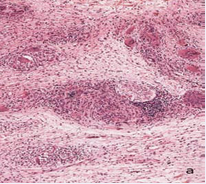

Biopsy of the anterior thorax showed a dermal infiltrate rich in giant cells and lymphocytes that touched the epidermis and compromised all the dermis and the hypodermis (Figure 2).

Figure 2a Skin biopsy of the trunk. Panoramic view showing granulomatous infiltration of dermis and hypodermis with abundant giant cells and lymphocytes.

Figure 2b Sub epidermal granulomas rich in giant cells with lymphocytes, some of which penetrate the basal epidermis.